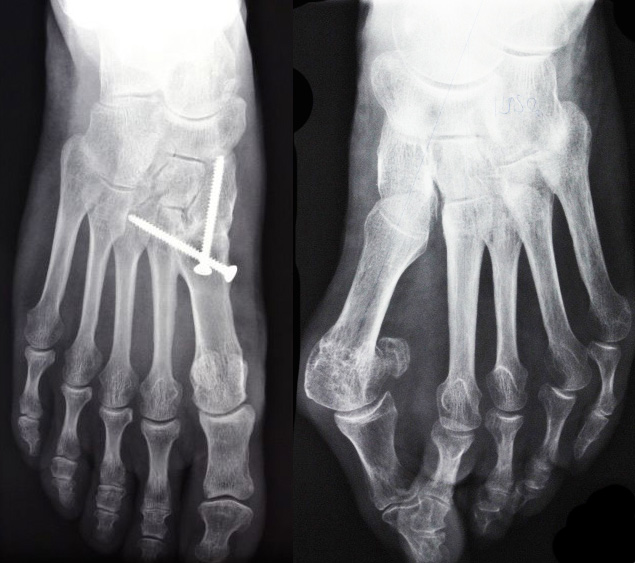

Auf dem Röntgenbild „Hallux valgus Röntgen vor und nach der OP“ erkennt man die Reorientierung und Stabilisierung des ersten Mittelfußknochens an die Fußwurzel und den zweiten Mittelfußknochen. Eine Vereinigung von erstem und zweitem Mittelfußknochen und erstem keilförmigen Fußwurzelknochen ist erreicht und bildet ein neues, stabileres Gelenk gegenüber dem Rückfuß.

Dies ist eine original Lapidusarthrodese. Gegenüber den symptomatischen Umstellungen des ersten Mittelfußknochens, wie Chevron-, Scarf- oder ähnlichen gelenkerhaltenden Osteotomien, ist sie ursachenorientiert und macht nicht nur einen geraden Großzeh, sondern auch den Fuß stabiler und leistungsfähiger. Die Hallux valgus Fehlstellung am linken Fuß ist noch unbehandelt.